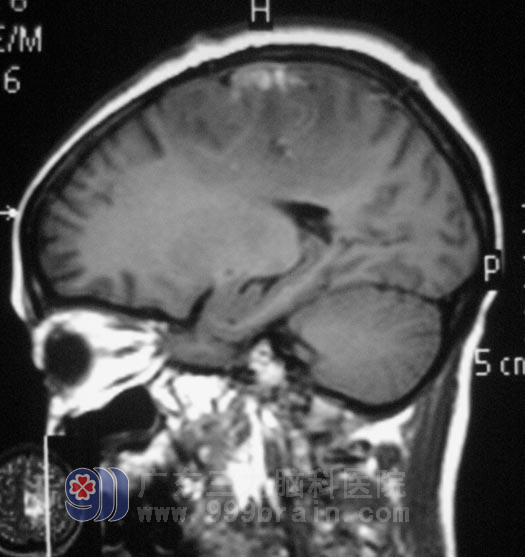

经脱水、抗炎等对症治疗后,陈女士已恢复了正常的行走,满意出院。术后经病理切片检查为:(左侧额定镰窦旁)脑膜瘤,局部细胞生长活跃(WHO I 级)。待修养一段时间后,她轻盈的舞步会又重新出现在小区里。http://www.999brain.com/